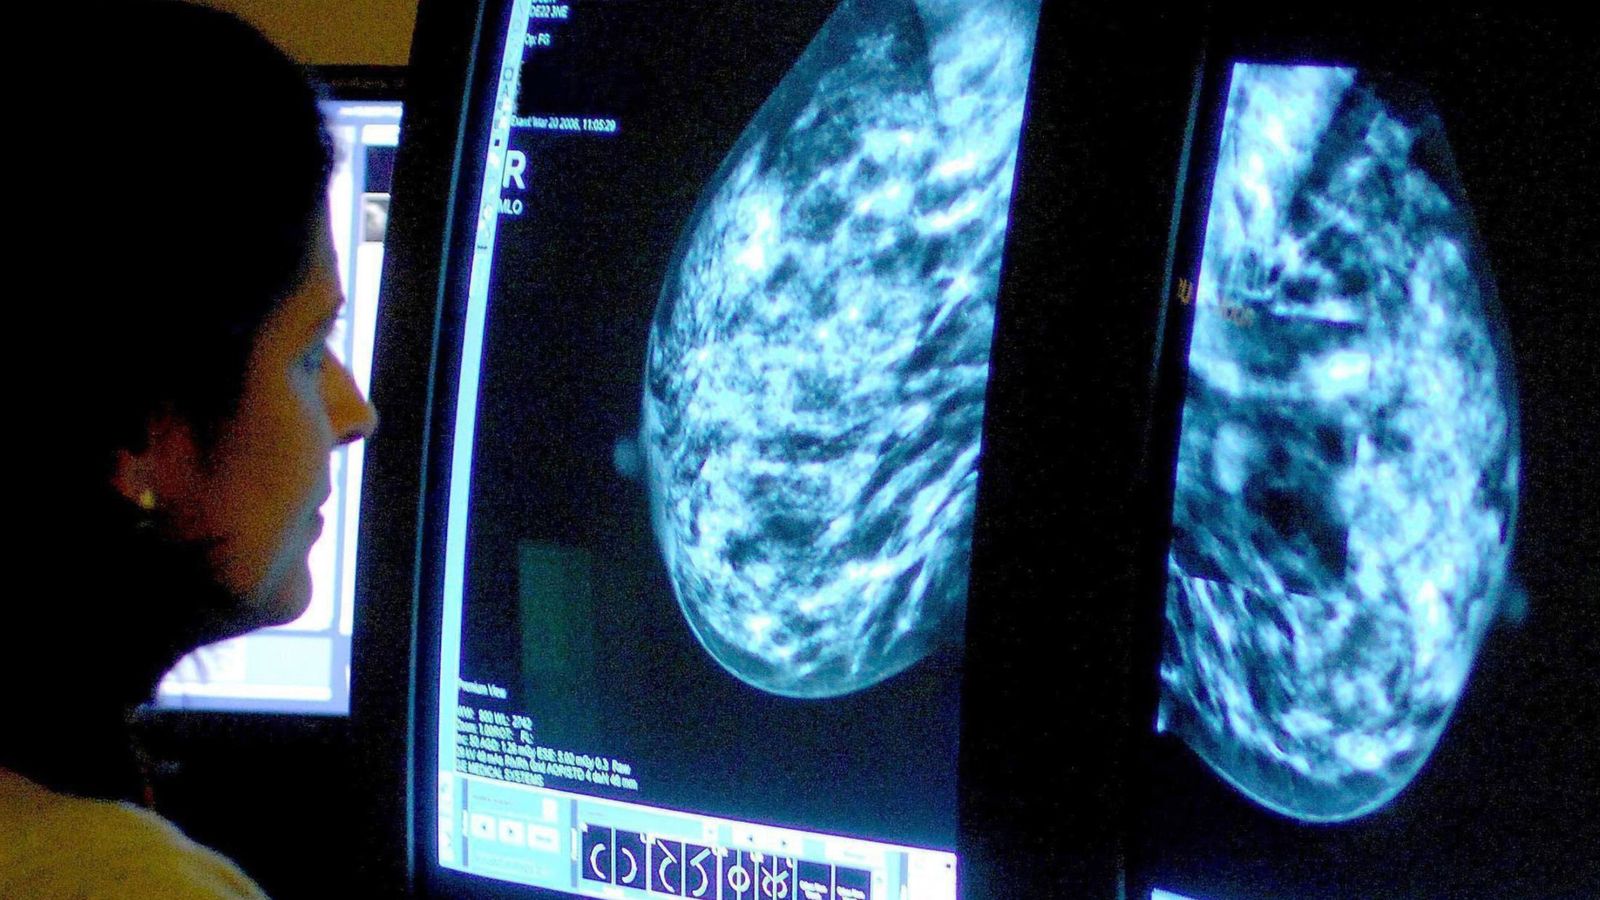

In 2022-23, almost 19,000 women across England were diagnosed with the disease thanks to the NHS screening programme.